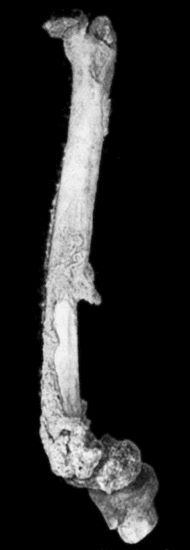

118.Shaft of the Femur after Acute Osteomyelitis 444

119.Femur and Tibia showing results of Acute Osteomyelitis 445